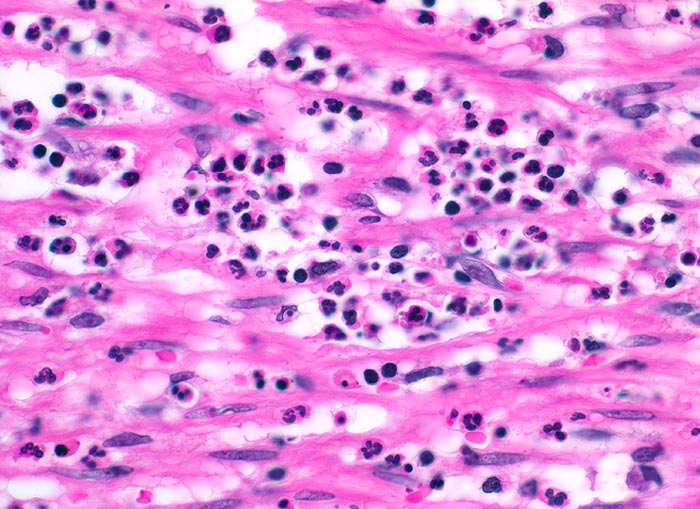

PathoPic ID 3432 - akute Appendizitis: phlegmonöse Entzündung

akute Appendizitis: phlegmonöse Entzündung

Entzündung / Reparatur

Appendix vermiformis

Darm, Anus

Die glatte Muskulatur der Appendixwand wird diffus infiltriert von neutrophilen Granulozyten.

Seit 6 Stunden Schmerzen im Unterbauch rechts mit zunehmender lokaler Druckempfindlichkeit. Übelkeit.

Histologie

400